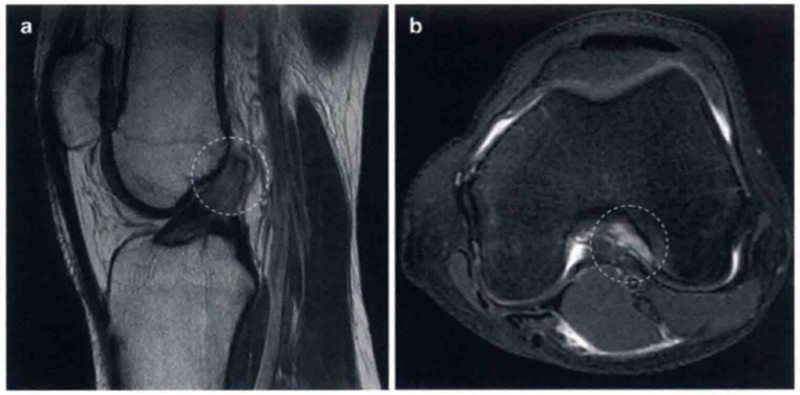

图3 a和b显示的为冠状位质子加权像和轴位T2像,并在关节镜下证明了为ACL股骨端撕裂。

在a中ACL股骨止点的信号增强,并且不能看到切带附着点(圆形区)。在b中ACL股骨附着点缺失(圆形区)。将图3b与图1b对比观察可显示正常的股骨止点